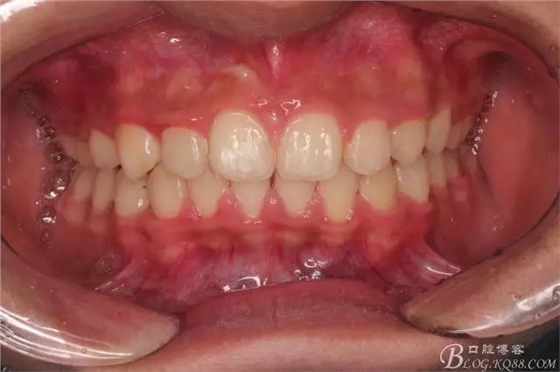

??茩z查:恒牙列,牙列式上下7-7.覆蓋二度,覆合三度,雙側磨牙關系二類,尖牙關系二類,下合3-3各牙間散在約1-1.5mm間隙,輕度唇傾,正面觀顯下頜頦部發(fā)育不足,側貌可觀察到下頜略顯后縮,上頜鼻唇角以及唇部大體正常。開口型向下,舌體正常,TMJ檢查及其它未發(fā)現(xiàn)異常。

看看口內照吧!真象“大暴牙”v假象“大暴牙”

三度深覆合,三度深覆蓋,尖牙,磨牙均二類關系!